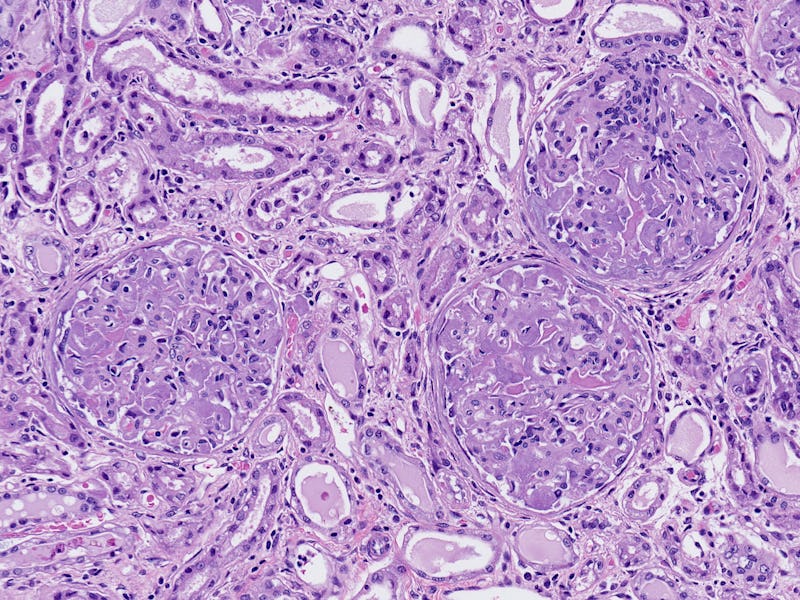

Human liver tissue with amyloidosis.